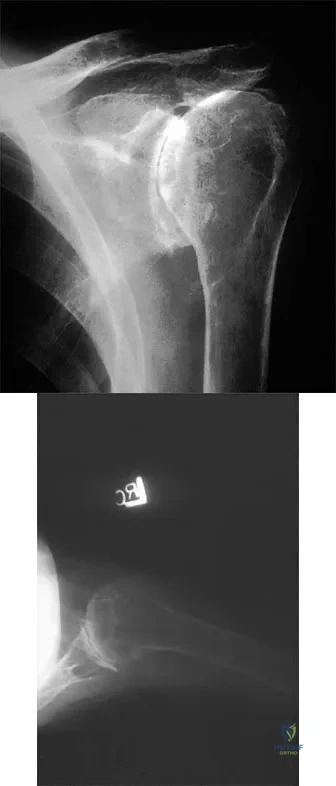

Question 30

A 55-year-old woman with polyarticular rheumatoid arthritis has had progressively increasing left shoulder pain for the past 2 years despite nonsurgical management. No focal weakness is noted during examination of the shoulder. AP and axillary radiographs are shown in Figures 47a and 47b. Treatment should consist of

Explanation